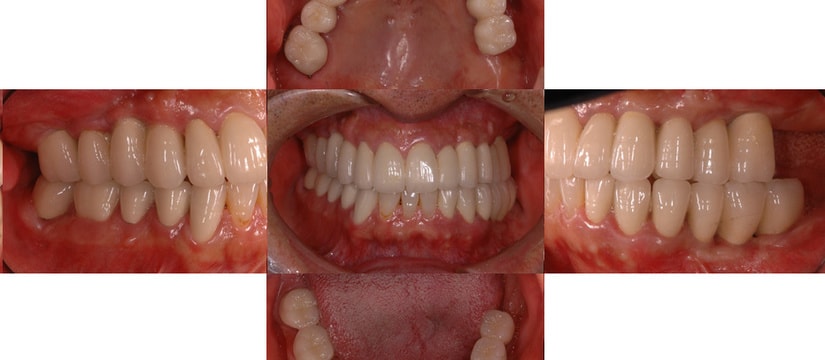

治療後

治療前のかみ合わせのままで治療しても長持ちしないこと、本来のかみ合わせから崩れてしまっていると判断し、お口の中を総合的に治療する治療方法を提案させていただき治療を行いました。

残すことが出来ない歯の抜歯などを行うと、すれ違い咬合という治療するには難しいかみ合わせであったことなど、仮の入れ歯などで咬合状態の経過観察などを行ったため治療期間は約2年ほどかかりました。

奥歯をインプラントにて治療し、よく噛めるようにしました。また、虫歯や歯の根の治療のやり直しを行いセラミックにて審美的に修復しました。